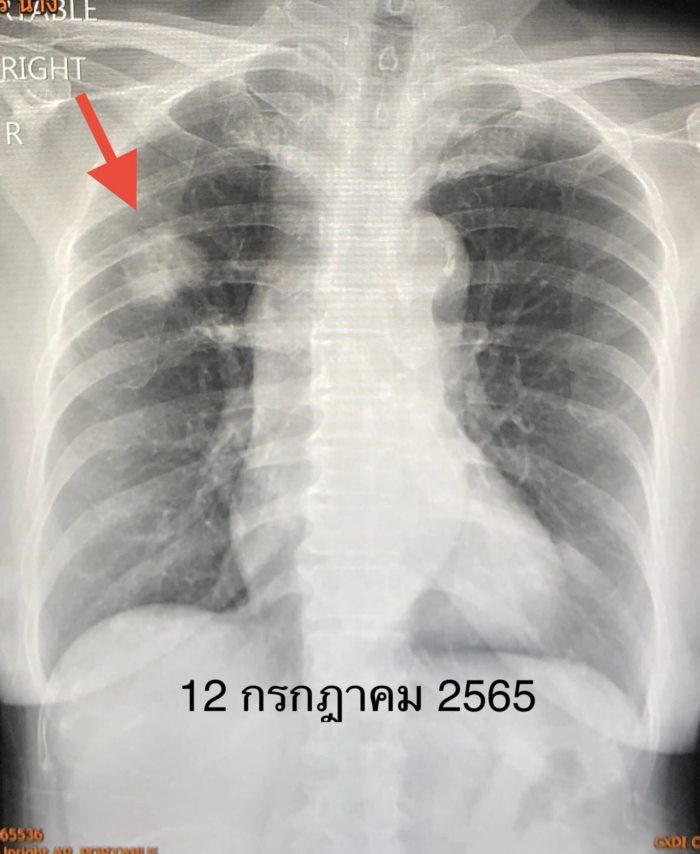

ผู้ป่วยหญิงไทย อายุ 69 ปี แข็งแรงดี ไม่มีอาการผิดปกติ ไม่สูบบุหรี่ ไม่มีโรคประจำตัว เอกซเรย์ปอดประจำปี พบก้อนในปอดข้างขวาด้านบนขนาด 2.2 × 2.7 × 2.5 เซนติเมตร เมื่อเอกซเรย์ด้วยคอมพิวเตอร์ พบต่อมน้ำเหลืองในช่องตรงกลางในทรวงอกโต ทำ PET scan ยืนยันก้อนในปอดและต่อมน้ำเหลืองบริเวณช่องตรงกลางในทรวงอก เจาะก้อนในปอดข้างขวา พบมะเร็งปอดชนิด adenocarcinoma ส่งตรวจการกลายพันธุ์ของยีนพบ EGFR exon 20 insertion mutation

สรุปว่าป่วยเป็นมะเร็งปอดระยะแพร่กระจายแล้ว ผ่าตัดไม่ได้ เนื่องจากเวลานั้นยังไม่มียามุ่งเป้าที่ใช้กับยีนกลายพันธุ์ชนิดนี้ จึงได้เริ่มยาเคมีบำบัดตั้งแต่ต้นเดือนสิงหาคม 2565 โดยให้ยาเคมีบำบัด ALIMTA และ Carboplatin ทั้งหมด 8 ครั้ง ก้อนในปอด เดือนตุลาคม 2565 มีขนาดเล็กลง ต่อมาเดือนมกราคม 2566 ก้อนในปอดกลับโตขึ้นอีก เนื่องจากยาเคมีบำบัดใช้ไม่ได้ผลแล้ว